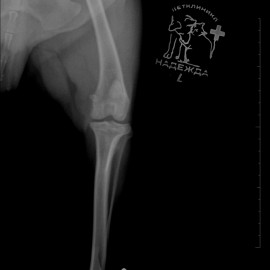

Наш пациент собака по кличке Артемон. Обратились с жалобами на остро развившуюся хромоту на заднюю левую лапу. После осмотра и рентгенологического исследования был поставлен диагноз - разрыв передней крестообразной связки левого коленного сустава. Была проведена операция- TPLO.

Снимки 1-2 до проведения операции.